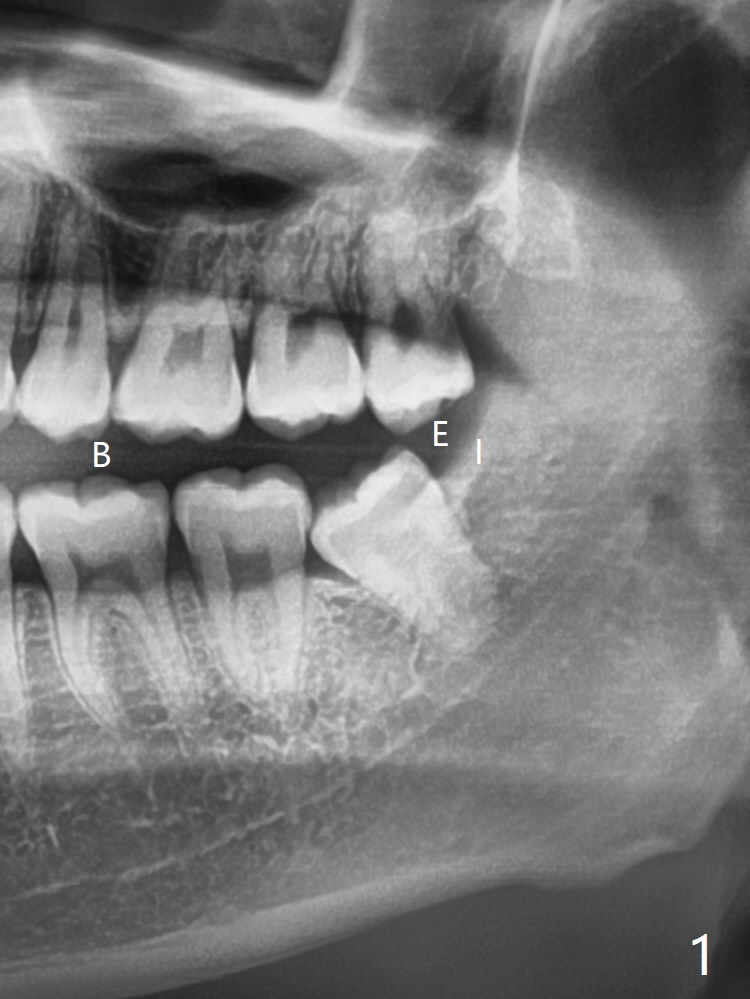

内(I)外(E)斜嵴位于下颌智齿远中,拔除后,内斜嵴近中密度增高,可能与外斜嵴重叠有关。左下牙槽窝放置骨胶原塞(图十)。